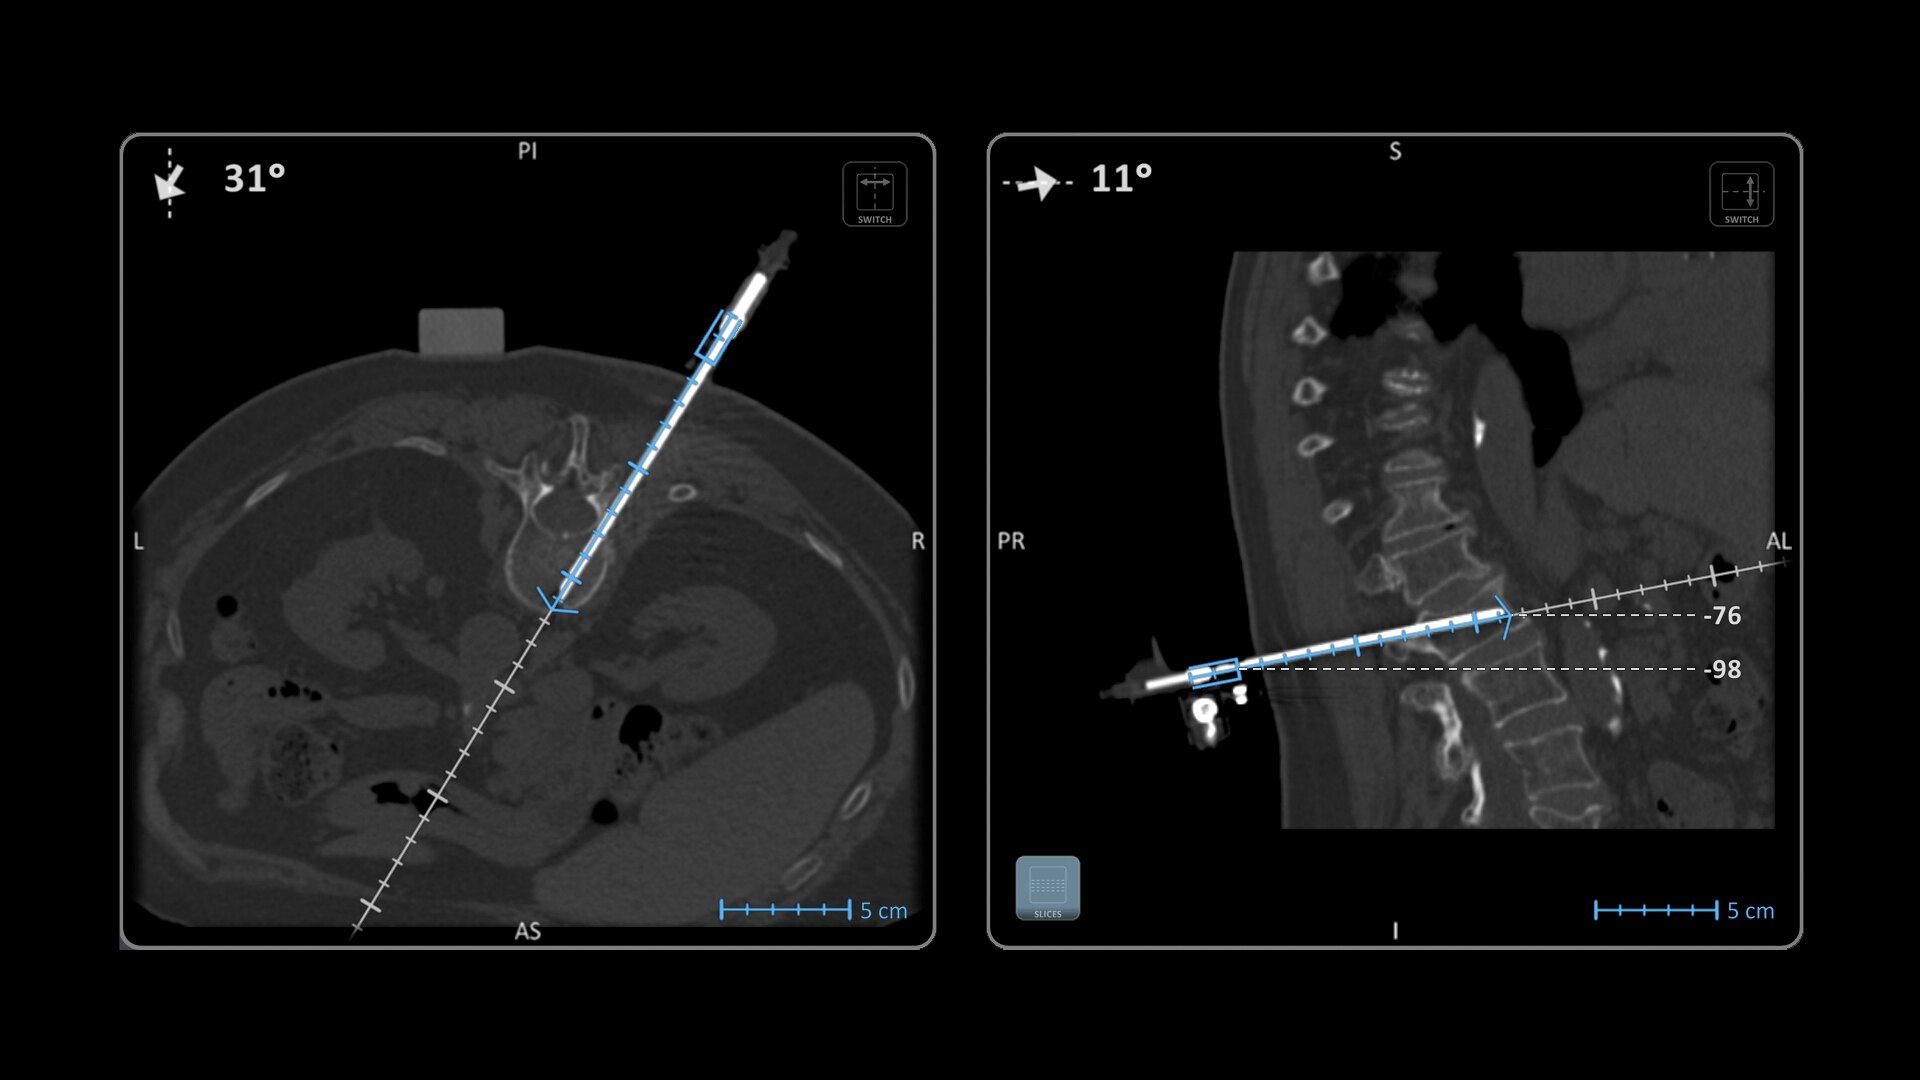

Imactis® CT-Navigation™ is an electromagnetic (EM) navigation solution for CT-guided percutaneous procedures

Imactis® CT-Navigation™ is designed to radically improve efficiency of Interventional procedures for clinicians and hospitals by increasing their accuracy.